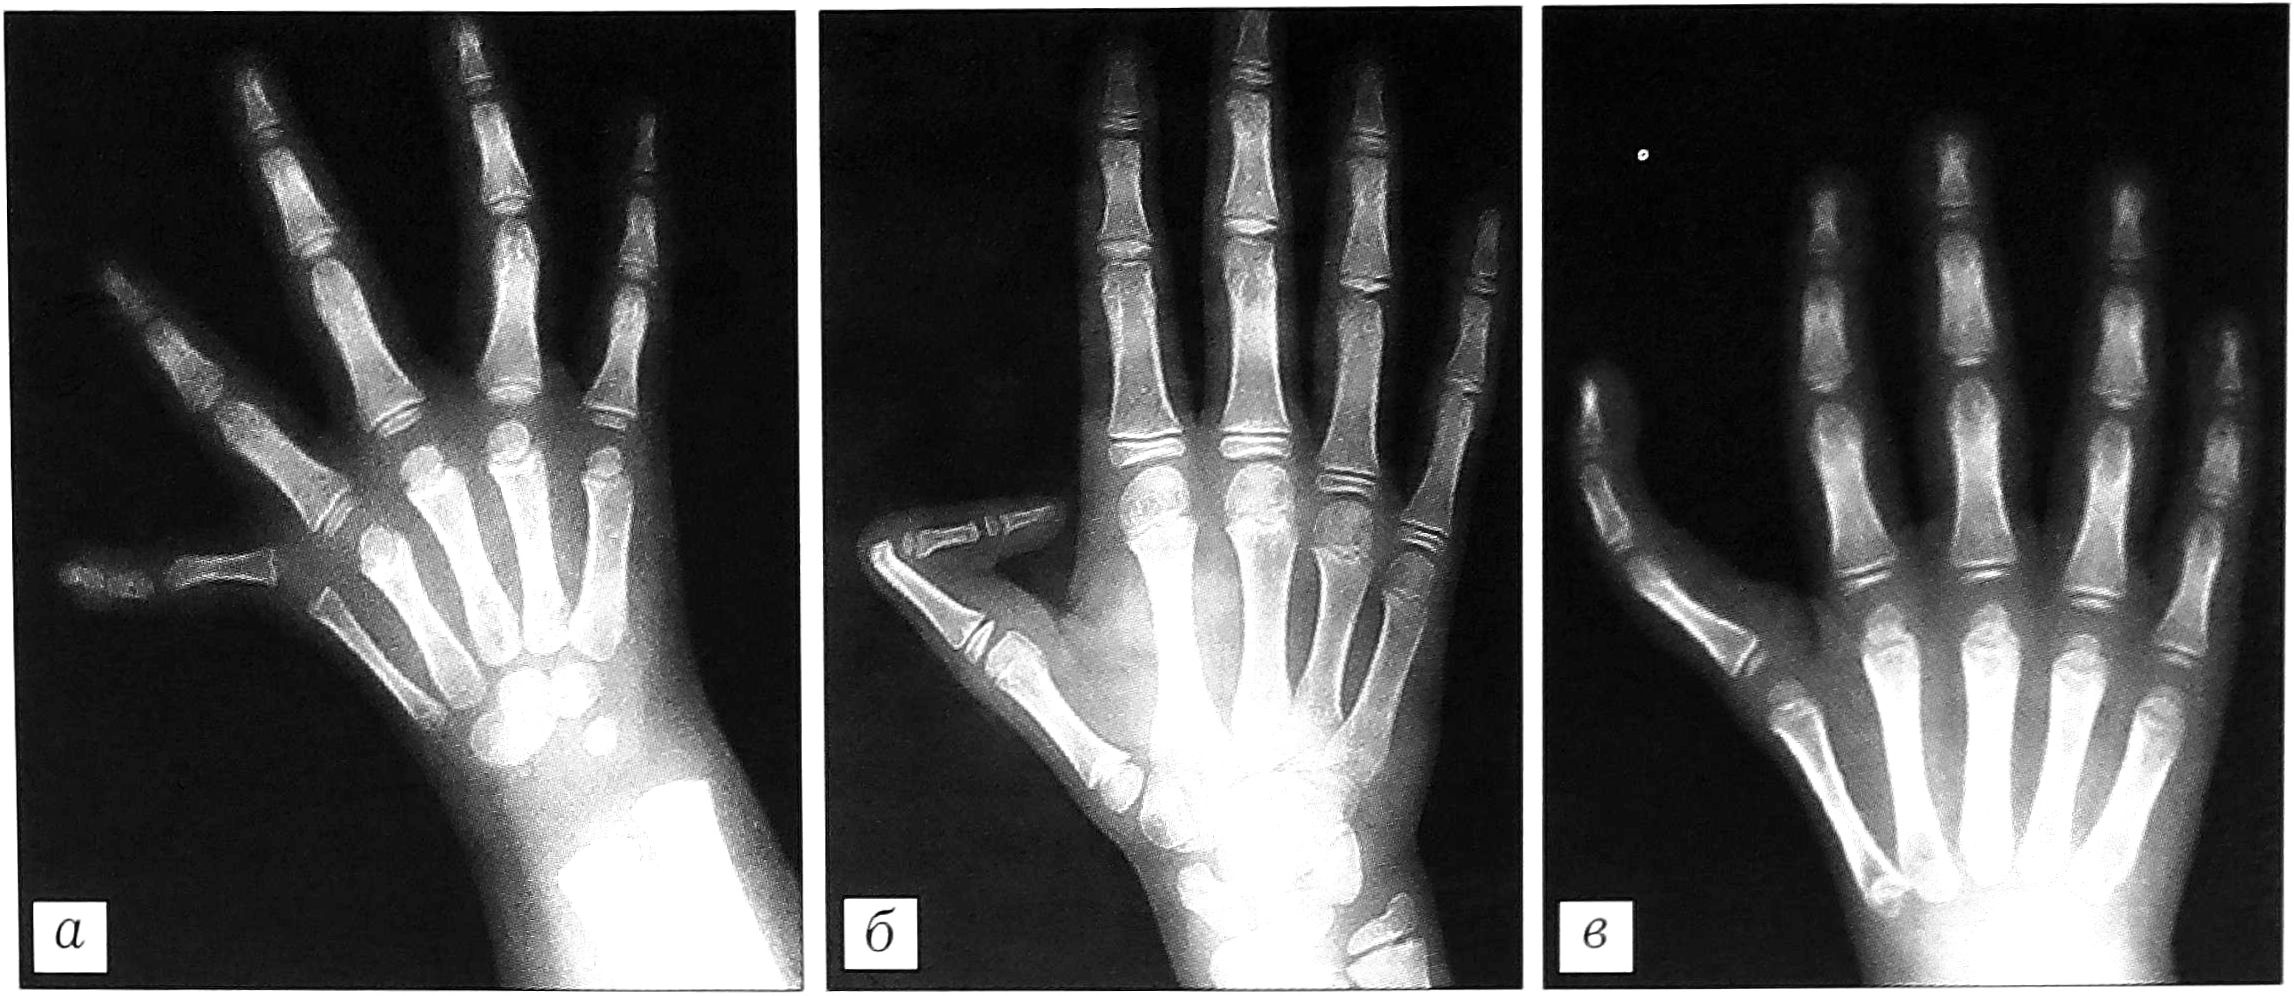

- Долихофалангеальная форма врожденного трехфалангизма I пальца кисти. Характеризуется следующими признаками (рис. 4):

- продольные размеры I пястной кости увеличены (на 15-30% от возрастной нормы), отмечается поперечная гипоплазия (на 15-40%), значительно реже — норма;

- I пястная кость имеет псевдоэпифиз;

- размеры дополнительной фаланги больше размеров дистальной фаланги (на 10-60%), ее форма — прямоугольная;

- продольные размеры I луча кисти увеличены на 15-40% от возрастной нормы;

- величина первого межпястного промежутка значительно уменьшена (реже нормальная).

Рис. 4. Долихофалангеальная форма трехфалангизма: а — с нормальным первым межпальцевым промежутком и увеличением I луча до 20% от возрастной нормы; б — с уменьшенным первым межпальцевым промежутком и увеличением I луча на 20-40% от возрастной нормы.

Продольные размеры основной фаланги, как правило, увеличены до 30%, дистальной — уменьшены до 30% от возрастной нормы. Выявлена корреляция между продольными размерами I луча и величиной первого межпальцевого промежутка: по мере увеличения первого показателя второй уменьшается.

Кроме того, нами выделена переходная форма от долихофалангеальной к брахимезофалангеальной, характеризующаяся, в отличие от перечисленных выше признаков долихофалангеальной формы, отсутствием поперечной гипоплазии I пястной кости, менее выраженным увеличением размеров дополнительной фаланги и I луча кисти в целом (до 20%) и отведением I пальца (рис. 5).

Рис. 5. Переходная форма от долихофалангеальной к брахимезофалангеальной.